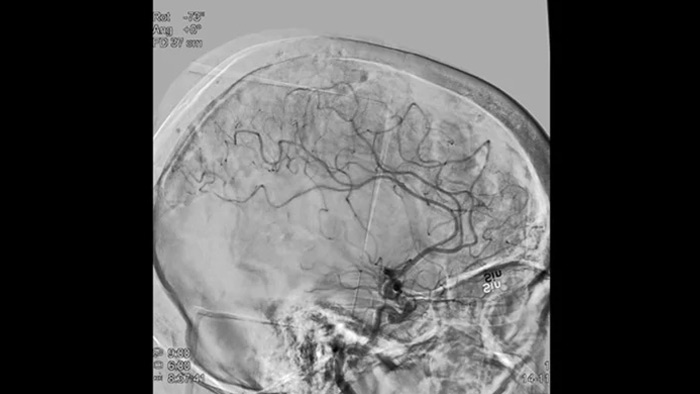

Scharfe Bilder dank 2D DSA mit ClarityIQ

2D DSA mit ClarityIQ

Die automatische Bewegungskompensation von ClarityIQ ermöglicht auch während Echtzeit-DSA scharfe Bilder der Gefäße und unterstützt so die sichere Entscheidungsfindung während Schlaganfallbehandlungen.